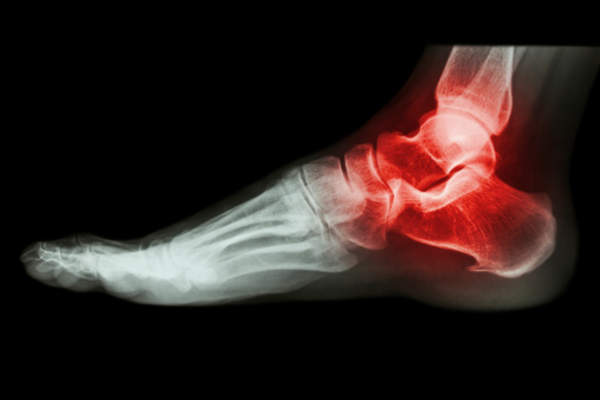

痛风